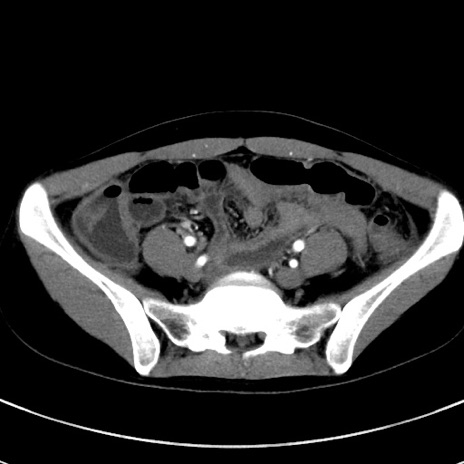

冠状断像

【症例】20歳代女性

【主訴】嘔吐、下腹部痛

【身体所見】意識清明、BT 37.2℃、BP 108/67mmHg、腹部:平坦、やや硬、下腹部正中から右にかけて圧痛あり、反跳痛軽度あり、tapping pain(+)。

【データ】WBC 13600、CRP 14.94